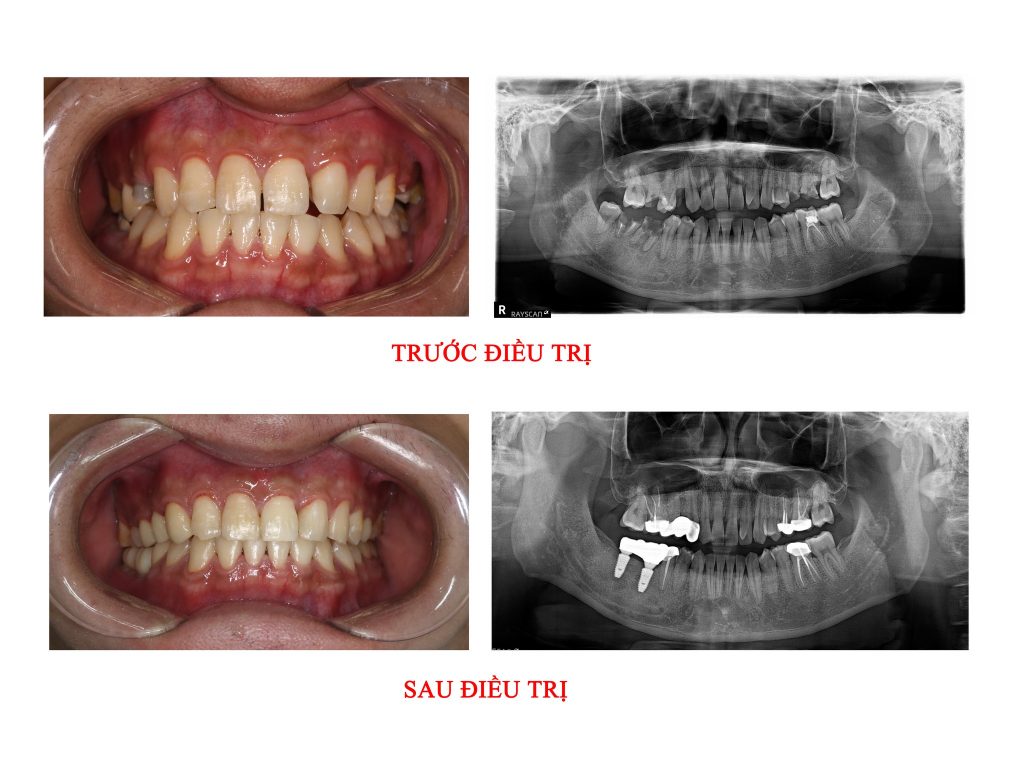

– Cấp độ 3: Nhổ răng, phục hồi lại bằng răng sứ hoặc Implant